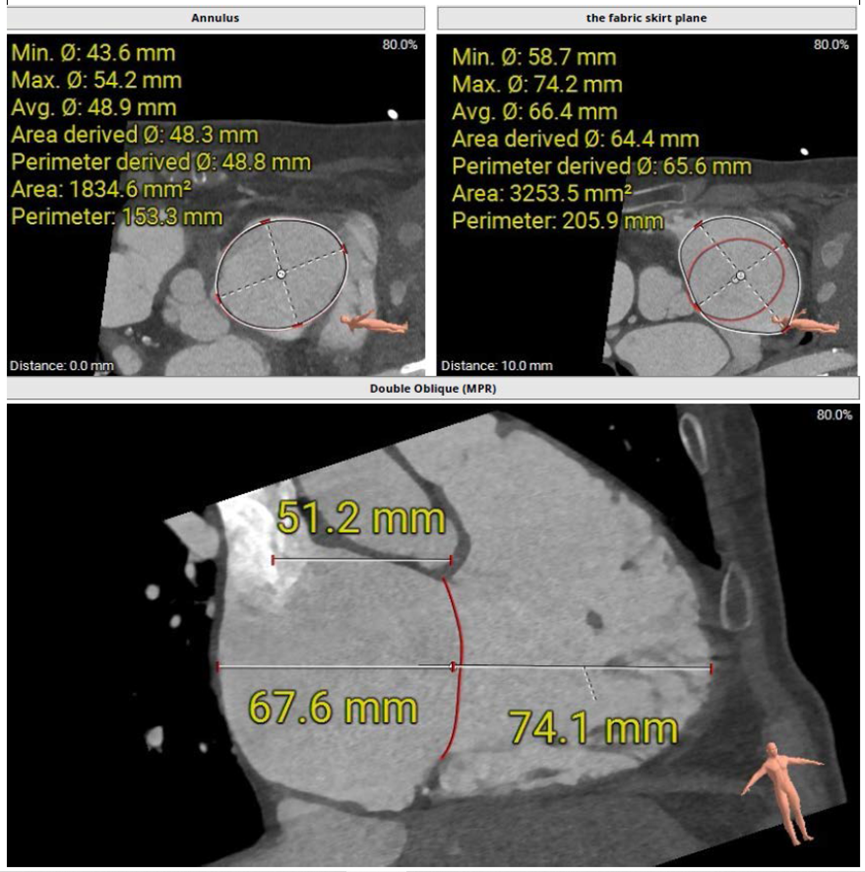

術前CT評估三尖瓣瓣環大小

術前超聲